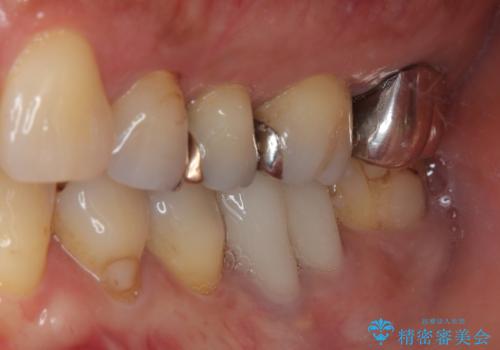

機能面、見た目共に満足していただきました。今後はメンテナンスで通っていただく予定です。

咬み合わせが強い方なので就寝時ナイトガードを使ってもらいます。